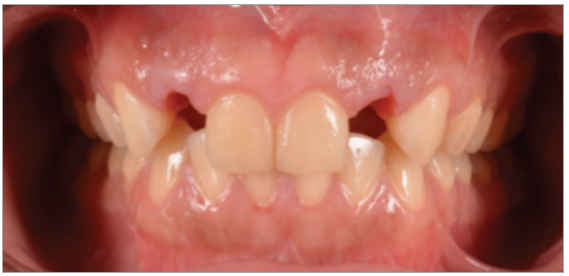

Paciente de sexo masculino de 24 años de edad, de raza mestiza, sin antecedentes sistémicos y oclusalmente estable, que fue transferido al servicio de Rehabilitación Oral del Posgrado y Especialización de la Universidad Peruana Cayetano Heredia, Lima, Perú. Recibió previamente tratamiento ortodóncico en el servicio de Ortodoncia y Ortopedia Maxilar por 6 años. Al examen intraoral presentó agenesia de las piezas 12 y 22 con evidencia de defectos óseos, presenta fenotipo periodontal grueso (figura 1). Al examen radiográfico se observa disminución generalizada de las raíces (Rizomicri), presenta ensanchamiento del ligamento periodontal generalizado (figura 2). Para el plan de trabajo para el diagnóstico se obtuvieron modelos de estudio primario, realizando el encerado para la planificación del tratamiento del sector anterosuperior. Al análisis tomográfico se evidenció poca disponibilidad ósea, motivo por el cual se planificó dos injertos en bloque de mentón con hueso particulado y plasma rico en plaquetas previo a la colocación de implantes dentales (figura 3 y figura 4). Pasado el tiempo de osteointegración (6 meses) se colocaron dos implantes Strong WS Cono Morse (SIN®, Sao Paulo, Brasil) de 3.5 mm x 11 mm. En la segunda fase, se confeccionaron provisionales de acrilico termocurado Vitalloy® (Vitacryl; A. Tarrillo Barba S.A., Lima, Perú) para el manejo de los tejidos blandos a nivel de las piezas 12 y 22, los cuales estuvieron fijados a un cilindro provisional de titanio (SIN®, Sao Paulo, Brasil) atornillado al implante, verificando la adaptación de este al implante mediante una radiografía periapical (figura 5). El cilindro fue recortado dando una altura de 6 mm, los provisionales fueron agujerados en el medio (figura 6), de tal forma que el cilindro calce en el medio del espacio edéntulo, se cubrió la entrada del cilindro con teflón (Golfo USA®) y se capturó el cilindro con acrílico de autocurado Duralay color 62 (Reliance Dental Manufacturing LLC, Illinois USA) (figura 7). Después del acrilizado se retiró el provisional, en la parte cervical se realizó un incrementó con resina fluida (Filtek™ Z350XT Flow - 3M ESPE Dental Products. St. Paul, Minnesota, USA) formando el contorno crítico a 2mm por debajo del zenit de los incisivos centrales de tal manera que entre los zenits de los incisivos centrales, laterales y caninos formen una zona triangular. El contorno subcrítico se realizó de forma convexa (figura 7 y figura 8). Se finalizó con el acabado y pulido del provisional con gomas de grano grueso (gris) y grano fino (verde) (Politip, Ivoclar-Vivadent; Schaan, Liechtenstein). Se manejó la conformación de los tejidos blandos en 2 citas mediante la adición por capas de resina compuesta (Filtek™ Z350 - 3M ESPE Dental Products. St. Paul, Minnesota, USA) a nivel del contorno crítico y subcrítico a las 2 semanas y 4 semanas de la instalación del provisional (figura 9 y figura 10). Se logró conformar las papilas interdentales, el contorno crítico y subcrítico observando que los tejidos se encontraran estables, sin inflamación, con el color de la encía igual a la encía adyacente; todo esto nos indicó que se podía realizar la impresión definitiva. La instalación final se realizó con coronas metal cerámicas cementadas (figura 11 y figura 12).